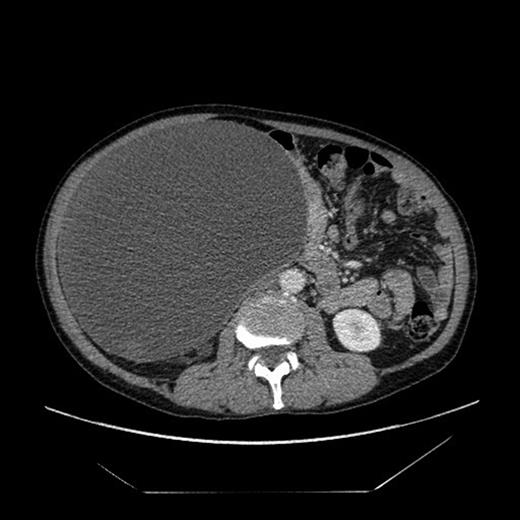

The CT (Figs 1–3) was performed identifying a unilocular, cystic lesion arising from within the right side of the abdomen. This lesion was distinct and not found to be related to any of the intra-abdominal organs. The radiological dimensions of the lesion were 22 × 20 × 19 cm. There were no radiological features to suggest acute or chronic pancreatitis. The findings were explained to the patient, and he was booked for laparotomy and excision of the cyst.

Axial slice from the CT imaging identifying the retroperitoneal pseudocyst.